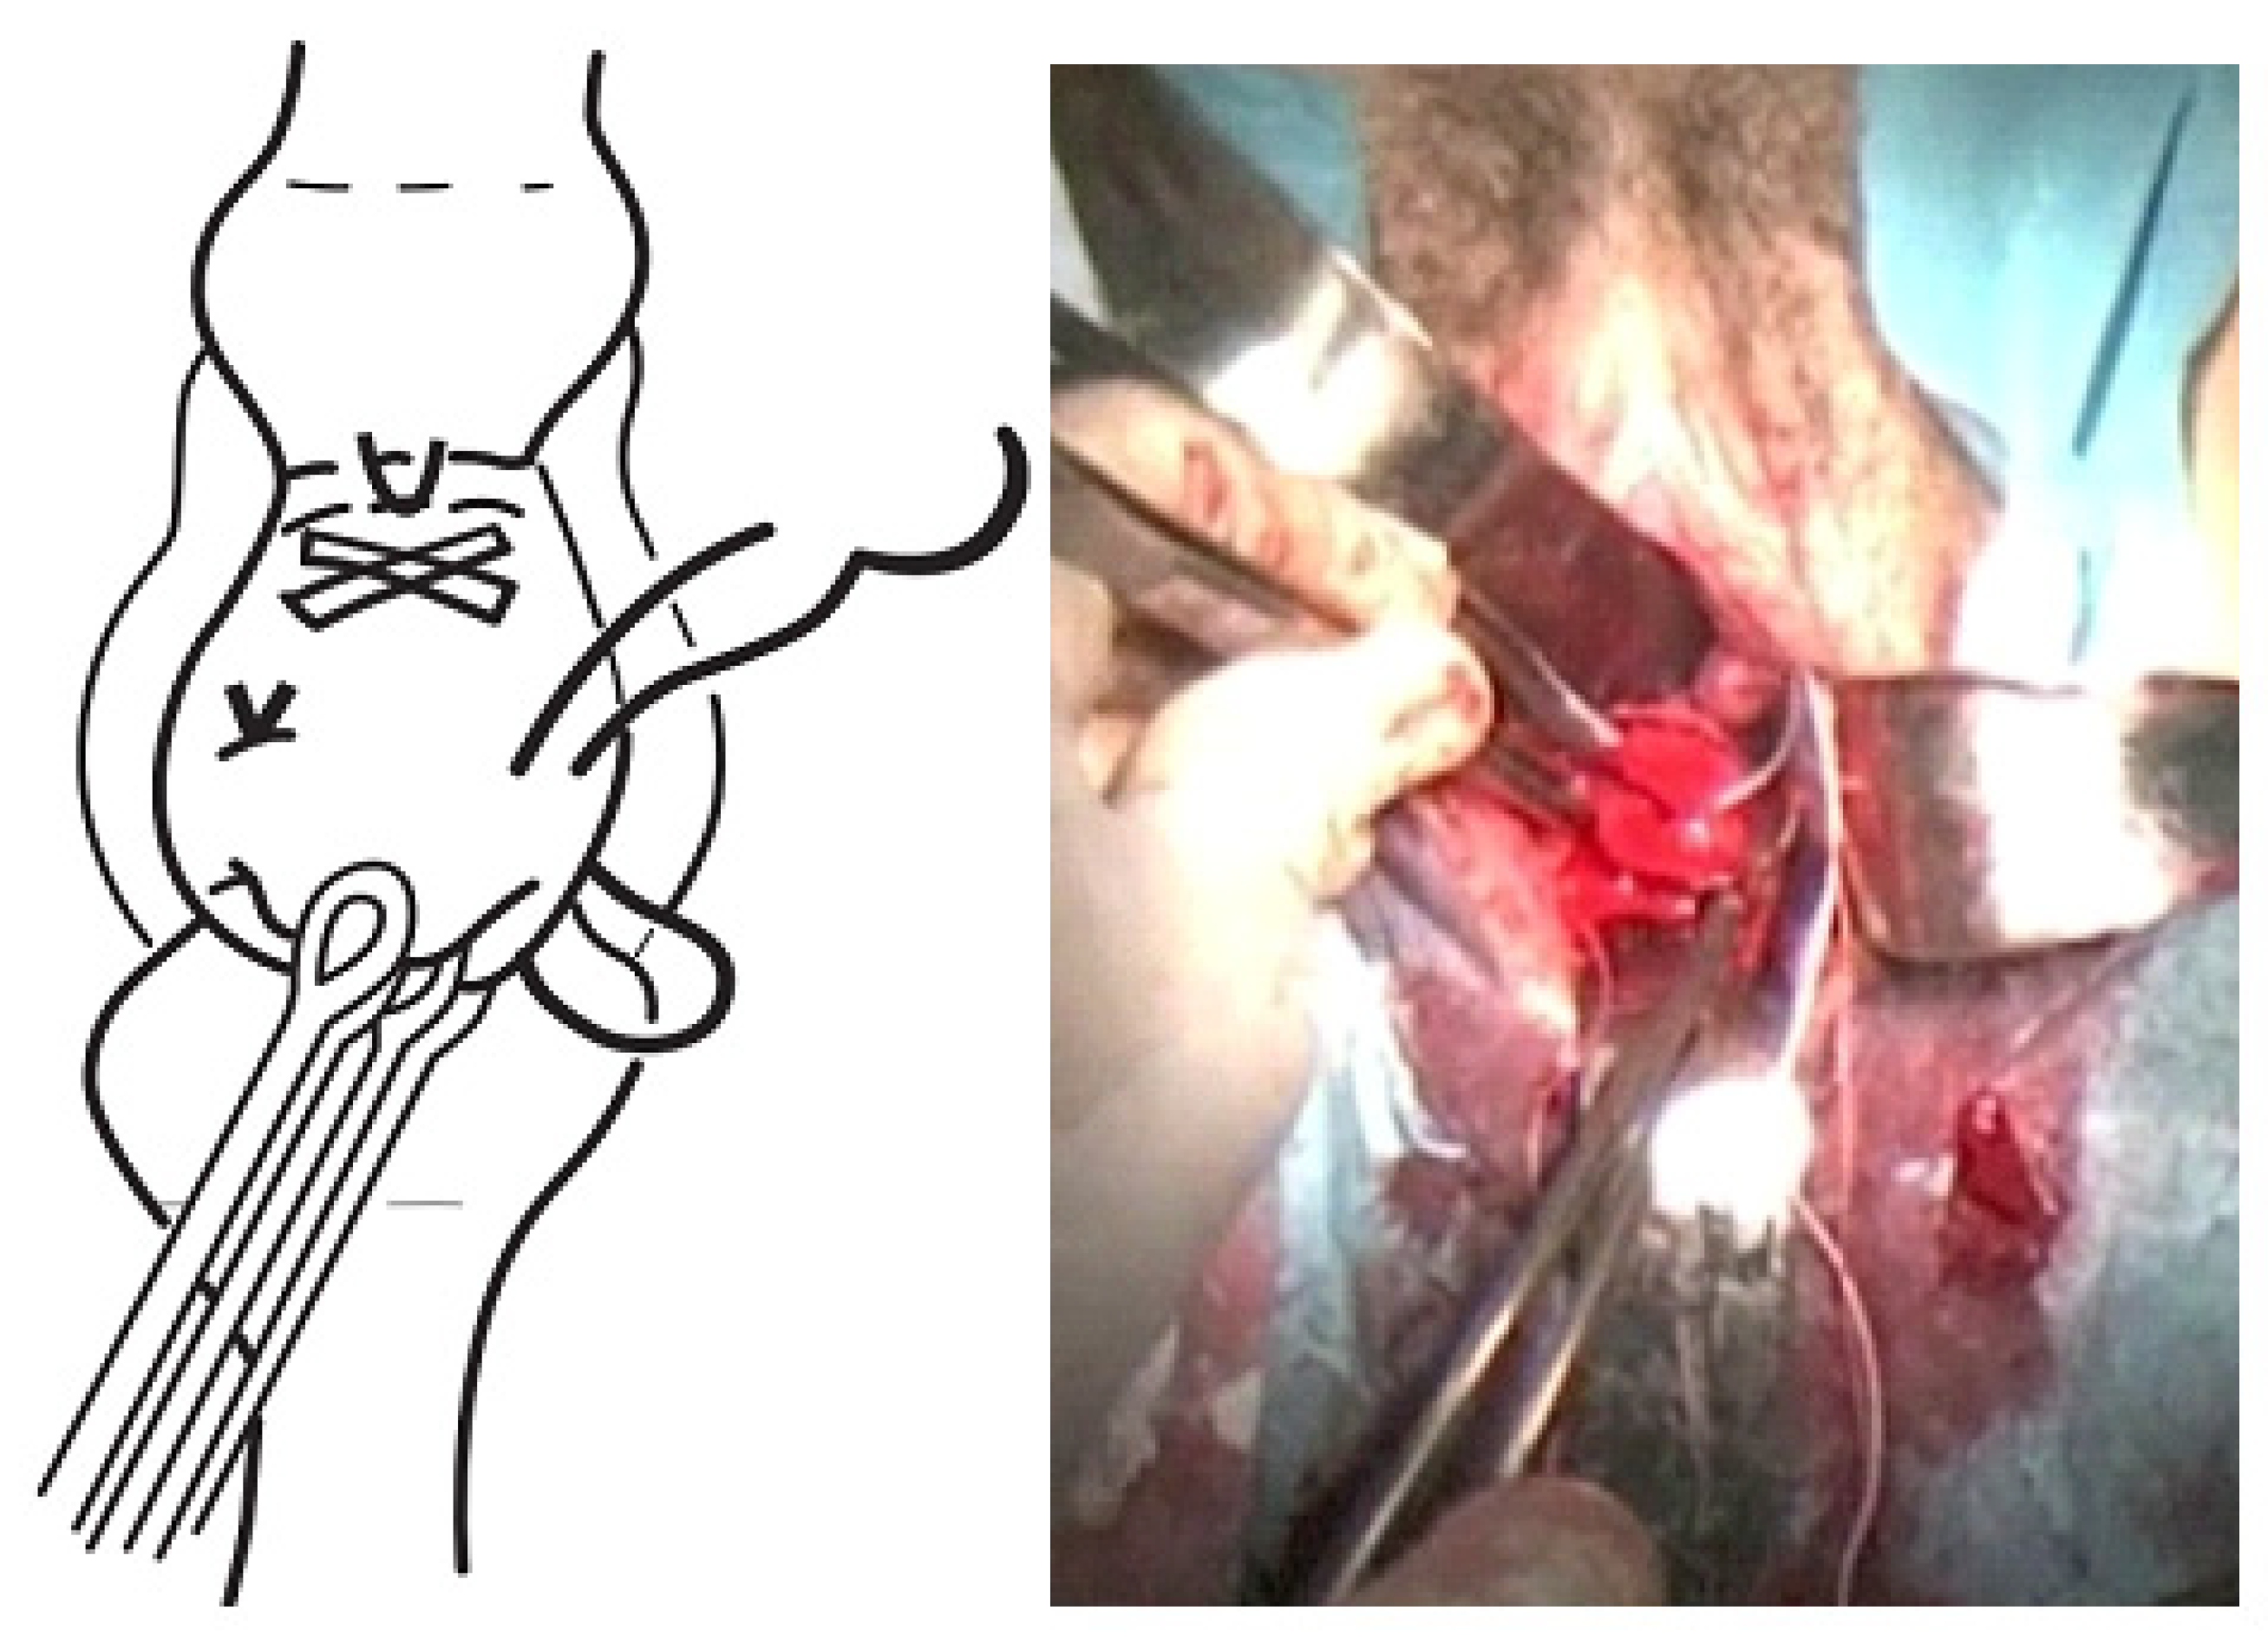

- A second cerclage was performed with Mersilene tape, which was attached approximately 1 cm below the previous cerclage. The stitches in this suture were designed to conglutinate the cervix, including the anterior and posterior lips at both commissures (8 to 11 o’clock on the left edge and 4 to 1 o’clock on the right edge). The point applied on the lower edge extended from 7 to 5 o’clock and was positioned as cranially as possible. The knot was located at 12 o’clock (Figure 3).